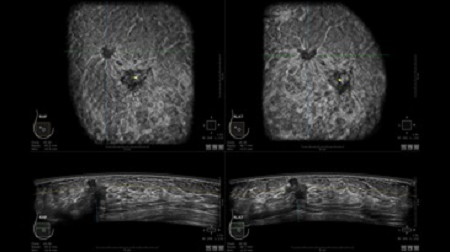

GE INVENIA ABUS – это современный УЗИ аппарат, который создан для точной и эффективной диагностики сканирования с высокой плотностью молочных желез. Выявляемость патологий раковых и предраковых стадий заболевания составляет 55%, что в конечном счете позволяет ставить врачу точные и своевременные диагнозы. Традиционные методы использования маммографии не показывают такой выявляемости, ограничиваясь лишь 3-38%.

УЗИ-аппарат GE INVENIA ABUS позволяет проводить максимально операторонезависимые процедуры, что значительно снижает риск неправильной постановки диагноза и сопутствующие издержки на обработку информации. Система готовит отчет в течение 3-х минут после сканирования, это безусловное преимущество по сравнению с обычным УЗИ сканером.